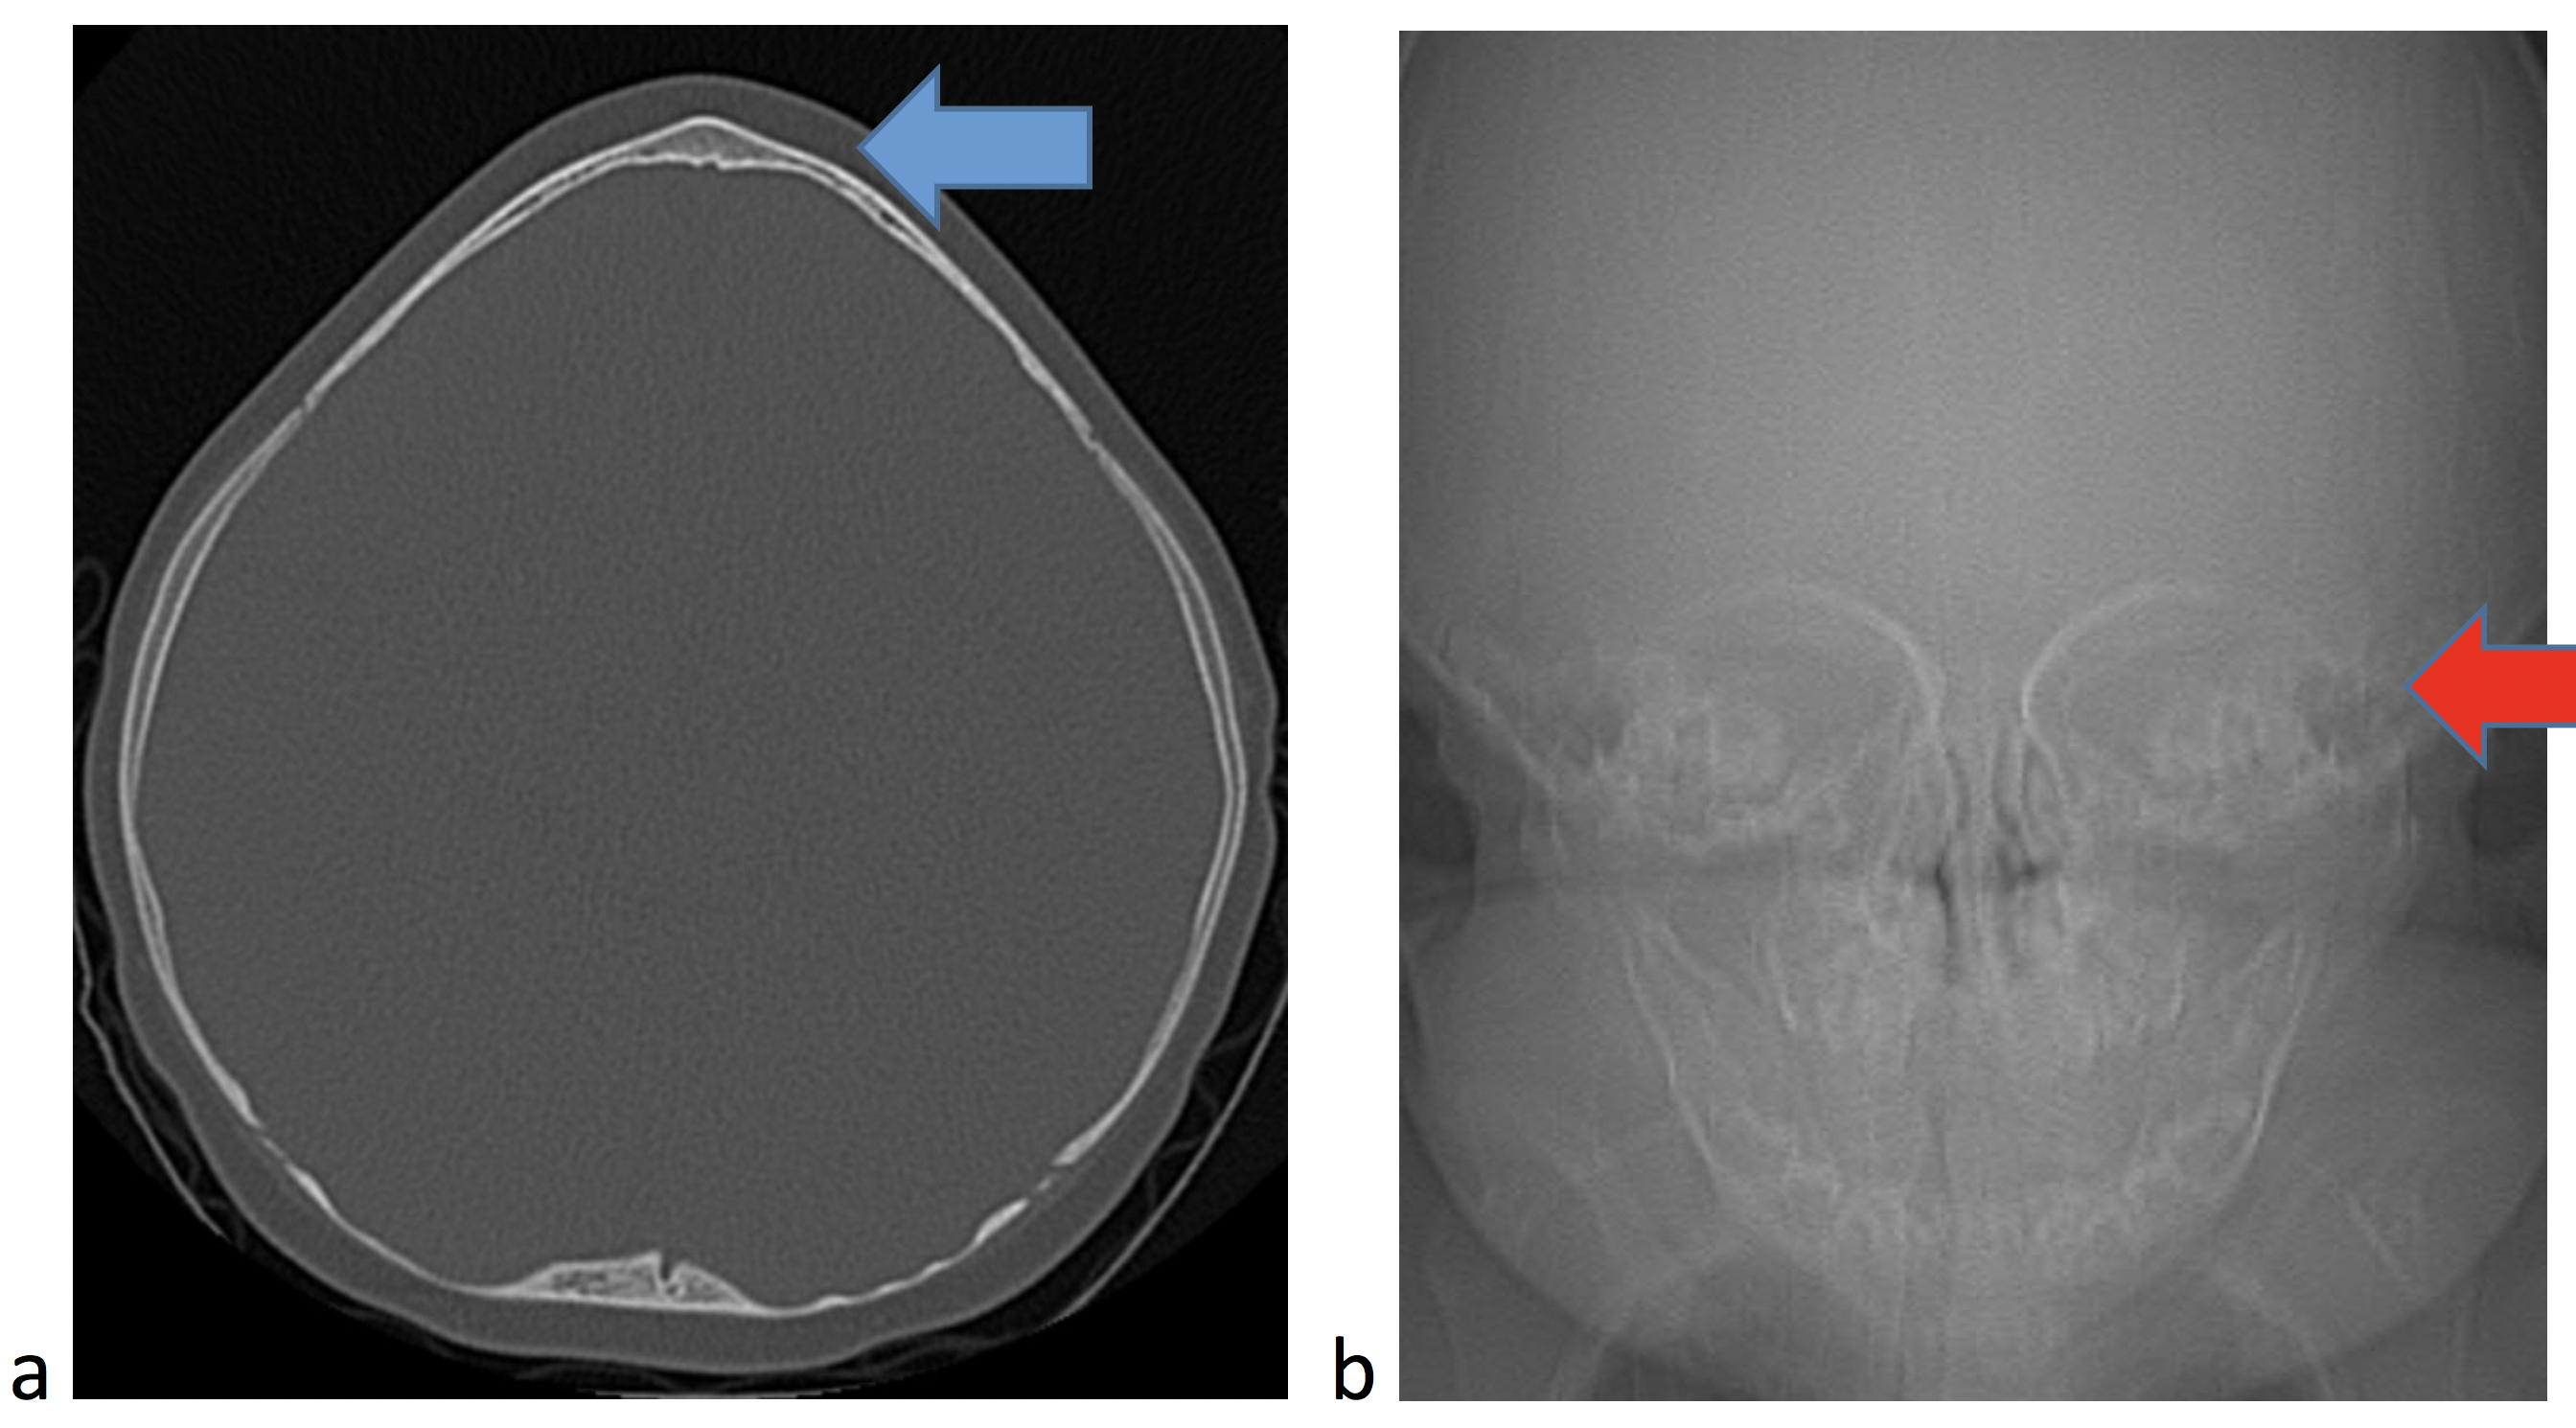

Some sutures normally close in infancy and childhood, such as the metopic suture. Even though this suture normally closes, it can also close prematurely leading to a pointed configuration of the frontal bone (Fig. 1a) and narrowing of the space between the eyes (Fig. 1b).